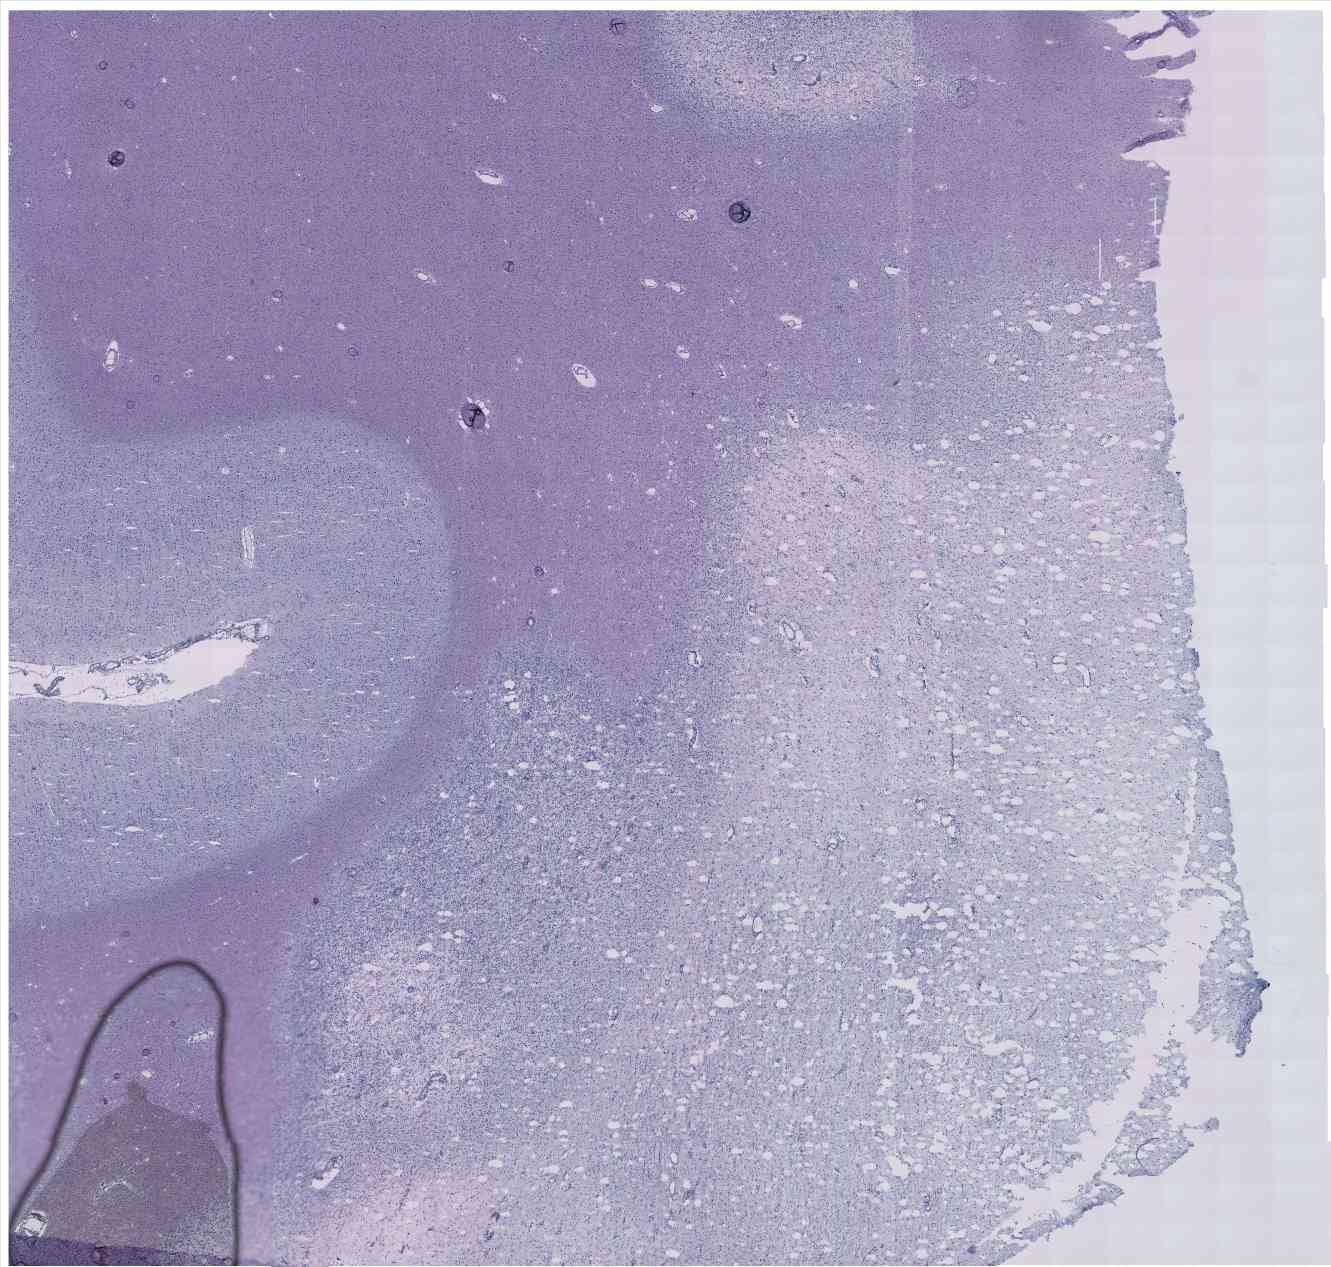

Chip 007 Well E2